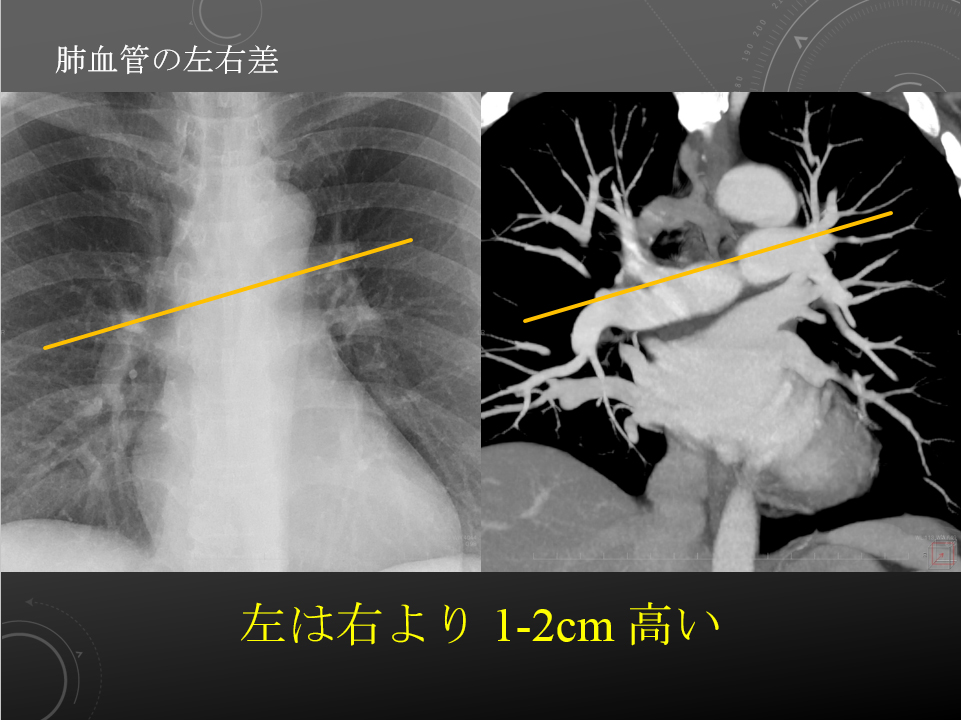

右肺動脈は中間気管支幹の前を横切りながら右下肺野に向かう。

左肺動脈は左主気管支内側を前から後ろに乗りこえ、下方に走行する。

左は右より 1-2cm 高い。

右肺動脈は中間気管支幹の前を横切りながら右下肺野に向かう。

左肺動脈は左主気管支内側を前から後ろに乗りこえ、下方に走行する。

左は右より 1-2cm 高い。